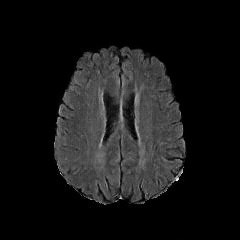

We use two popular medical imaging datasets primarily used for the evaluation of lesion segmentation: the Multimodal Brain Tumor Segmentation Challenge 2018 dataset (BratS18) [21, 2] and the Liver Tumor Segmentation Challenge dataset (LiTS).

BratS18.

The BratS18 dataset provides 210 high grade glioma (HGG) and 75 lower grade glioma (LGG) MRI with binary masks for the tumor (or lack of tumor). Each 3D MRI contains 155 slices of size 240×240240240240\times 240. Not every slice contains a tumor, and therefore healthy MRI are provided by this data as well. We use the FLAIR modality image for all the experiments because the entire tumor is represented well by this modality.However, we also show more experimental results on other modalities, where the ANT-GAN provides impressive visual quality. A more detailed medical description of the data can be found on the challenge website.111https://www.med.upenn.edu/sbia/brats2018.html

Aside from the difference in imaging tissue and modality of these two data sets, the tumor regions on the CT images are of different shape and size, as can be seen in Figure 4. Also, many CT scans are acquired in a way that introduces greater noise-like artifacts than MRI. For each dataset, 80%percent8080\% of randomly selected data are used for training and the resting 20%percent2020\% for testing.